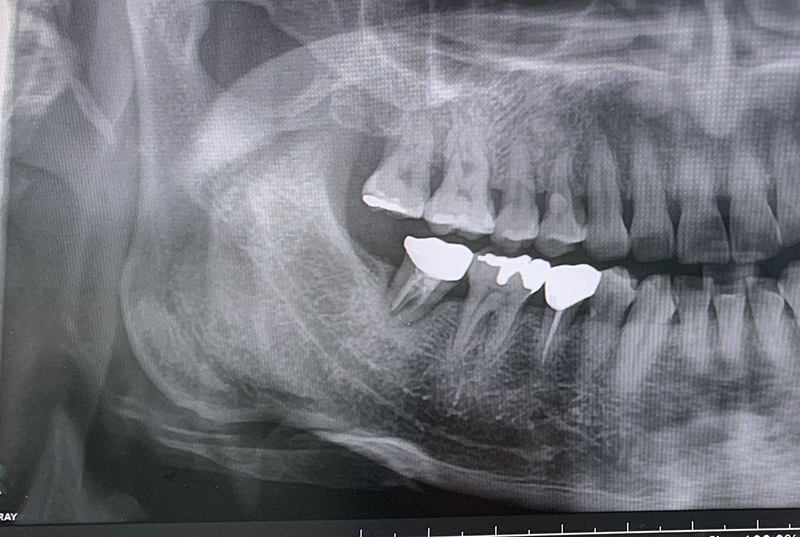

30대 초반쯤 사랑니 때문에 조금 아파서 회사 근처의 치과를 갔었는데 엑스레이를 찍어보니 옆으로 누운 치아라여기서는 힘드니 구강내과 전문의가 있는 조금 큰 병원으로 가서 빼라고 했었다. 나름 난이도가 있는 수술이라 잘하는 곳에 가서 뺏는데 저것이 개인적으로 생각하기에 옆으로 누운 사랑니의 위치가 옆 어금니의 잇몸뼈인 치조골까지 영향을 주는 바람에 치조골이 약해진 듯했다. 참고로 치아가 있는 곳의 없어진 치조골은 생기지는 않는다.

나의 경우 위의 사랑니의 영향도 조금이나마 있었겠지만 담배도 무척 많이 피었던 시기였고, 친구들과 음주도 자주 할 때였었다. 그리고 30대 초반이라 아직 젊었었으니 스케일링 등 치아관리를 잘하지 않았었다. 그러다가 결국 위의 사랑니 옆의 어금니에 치주염이 시작됐다. 처음에는 음식을 씹을 때만 조금씩 아프더니~ 피곤할 때나 간헐적으로 어금니 쪽이 욱신거렸다. 처음에는 나름 견딜만했으나, 갈수록 아프기 시작해서 치과에 방문해 잇몸치료를 하기 시작했다. 의사 선생님 말씀이 염증이 심해서 치조골 쪽이 거의 다 녹아서 치아가 흔들린다고 했다. 오래가지 않아 빠질 것이나 그래도 나름 최대한 살보 자고 하셨는데, 나름 유명한 치과를 가서 잇몸 레이저 치료까지 수시로 받았었다. 조금 괜찮아진 것 같더니~ 거의 막판에 무진장 아팠던 기억이 난다. 잇몸치료를 하고 마취가 풀리니 이건 완전 내 생에 그렇게 아팠던 적이 없었다. 그러다가 뜨거운 물, 차가운 물은 기본이고 미지근한 물이라도 마셔도 그 치아에 닷기만 하면 시리고 아팠다. 이것이 바람만 불어도 치아가 아프다는 풍치였던거 같다.